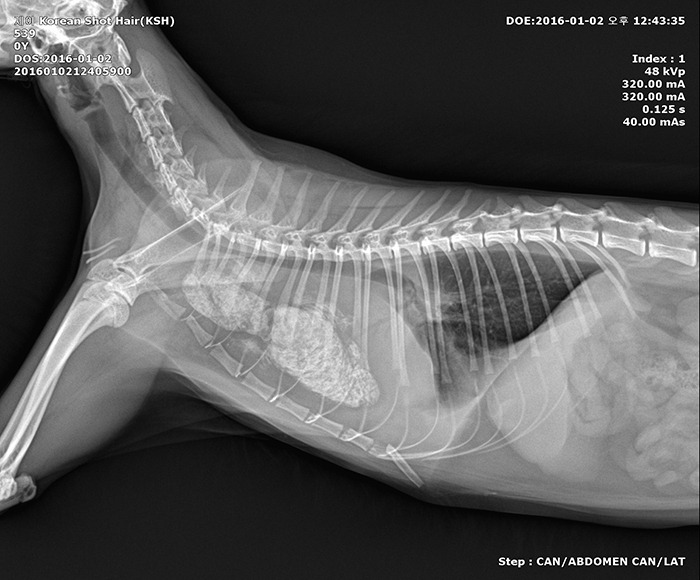

동물병원에서는 심장병부터 거대식도증, 복막염까지 다양한 병명이 짐작으로만 오르내렸다. 정확한 진단을 위한 검사 비용이 40만 원이 넘게 나왔지만 엑스레이에 찍혀 있는 몸속 하얀 덩어리의 정체는 알아낼 수 없었다. 깨끗하게 보여야 하는 폐가 뿌옇게 차 있고, 하얀 덩어리가 심장을 가리고 있어 심장 초음파 검사에서도 심장을 볼 수가 없다는 것이 새벽 1시까지 진행된 검사에서 나온 결과였다.

아… 이 하얀 부분이 뭔지 통 모르겠네요. 하는 선생님의 말에, 선생님이 모르면 도대체 누가 아는 건지 초조했다. 일단 가쁜 호흡은 폐에 차 있는 흉수 때문으로 보여 주사기로 흉수를 뽑았고, 그러고 나서 다시 찍은 엑스레이에서는 폐가 조금 깨끗해져 보였다.

1.jpg 흉수 제거 후의 엑스레이 촬영